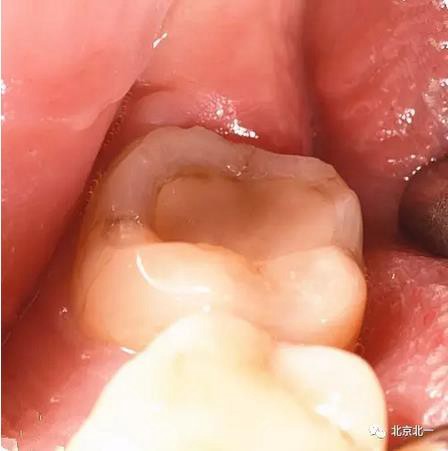

圖十:實際情況:看到么在第二磨牙頰側(cè)接近近中區(qū)域。關(guān)鍵牙顏色和骨顏色一致, 只有牙冠部分是白色能看出來, 但是它卻深深的把頭埋下。